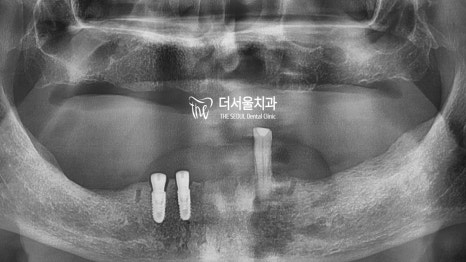

환자의 초진 사진을 살펴보니,

남아있는 치아가 하나밖에 없었습니다.

컴퓨터 분석을 통해 식립 위치를 정한 뒤

본격적인 치료 과정에 들어갔습니다.